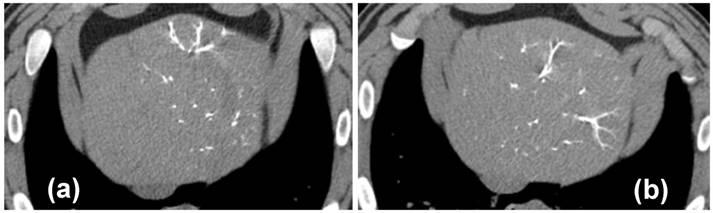

No biliary ductal dilatation was noted on the Day 0 CTs of unloaded or drug loaded beads with targeted lobe sizes similar between both. Biliary dilatation was seen on 4/4 Day 30 CTs of the VERB100 group and 0/3 the Day 30 CTs of the ROB control group. The Day 90 CTs of the VERB100 group show 2/3 with biliary dilatation. The Day 90 CTs of the unloaded control group show 2/3 with biliary dilatation. Lobe size of both control group and VERB100 group were compared to initial appearance and adjacent non-targeted lobes. There was a reduced size of the targeted lobe in 6/7 VERB100 group (Figure 5(b)). The control group demonstrated decreased size in 0/6. This was noted to be present on Day 30 and Day 90 CTs. Areas of decreased perfusion on initial CT demonstrate decreased size on follow up CT. Again, the finding can be attributed to more effective embolization which would decrease lobule and hence lobe size.

Interlobular fibrosis was observed for both unloaded (1/3 animals, Figure 6(a)) and the VERB100 group (4/4 animals, Figure 6(b)) at 30 days and this persisted at 90 days (3/3 and 2/3 animals respectively). This was often associated with bile duct hyperplasia, encircling lobules that were reduced in size, resulting in a macroscopic reduction in the size of the treated liver lobe (Figure 6(b, c)). Reduced lobule size in the treated sections of liver in the VERB100 group (3/4 animals) was characterized by smaller lobules with disorganized trabeculae but no evidence of hepatic degeneration. The finding correlated to the reduced lobe size noted following radiologic evaluation (Figure 5(b)). The shrunken lobules were lined by small bile ducts extending from the portal spaces (identified as bile duct hyperplasia, 3/4 animals) and/or variably sized bundles of fibrosis (interlobular fibrosis, 4/4 animals, Figure 6(c)). In addition, large bile ducts were occasionally dilated (Figure 6(b)) and were surrounded or had inflammatory infiltrate in their lumen (2/4 animals, Figure 6(d)). The bile duct dilation was also noted following radiologic evaluation (Figure 5(b)). None of these treatment-related findings were present in the untreated liver section and are consistent with impaired blood flow with subsequent necrosis and regeneration.

Figure 5

(a) MDCT axial image of portal venous phase post contrast, 1 hour post-embolization with VERB100, yellow arrows point to areas of decreased hepatic parenchymal enhancement; (b) MDCT axial image of portal venous phase post contrast, red arrows indicate dilated bile ducts, yellow arrows show the reduced left liver lobe size 30 days post-embolization.